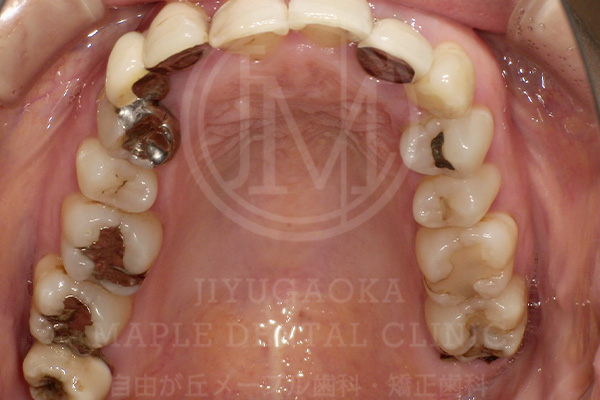

前述した通り、銀歯治療は構造的・素材的な特性から、虫歯の再発(=二次虫歯)リスクが高くなる傾向があります。ここでは当院にご来院された方の銀歯の下で虫歯が広がってしまっていたケースを紹介します。

銀歯の下で虫歯が

広がってしまっていた症例

銀歯を外す前

銀歯を外した後